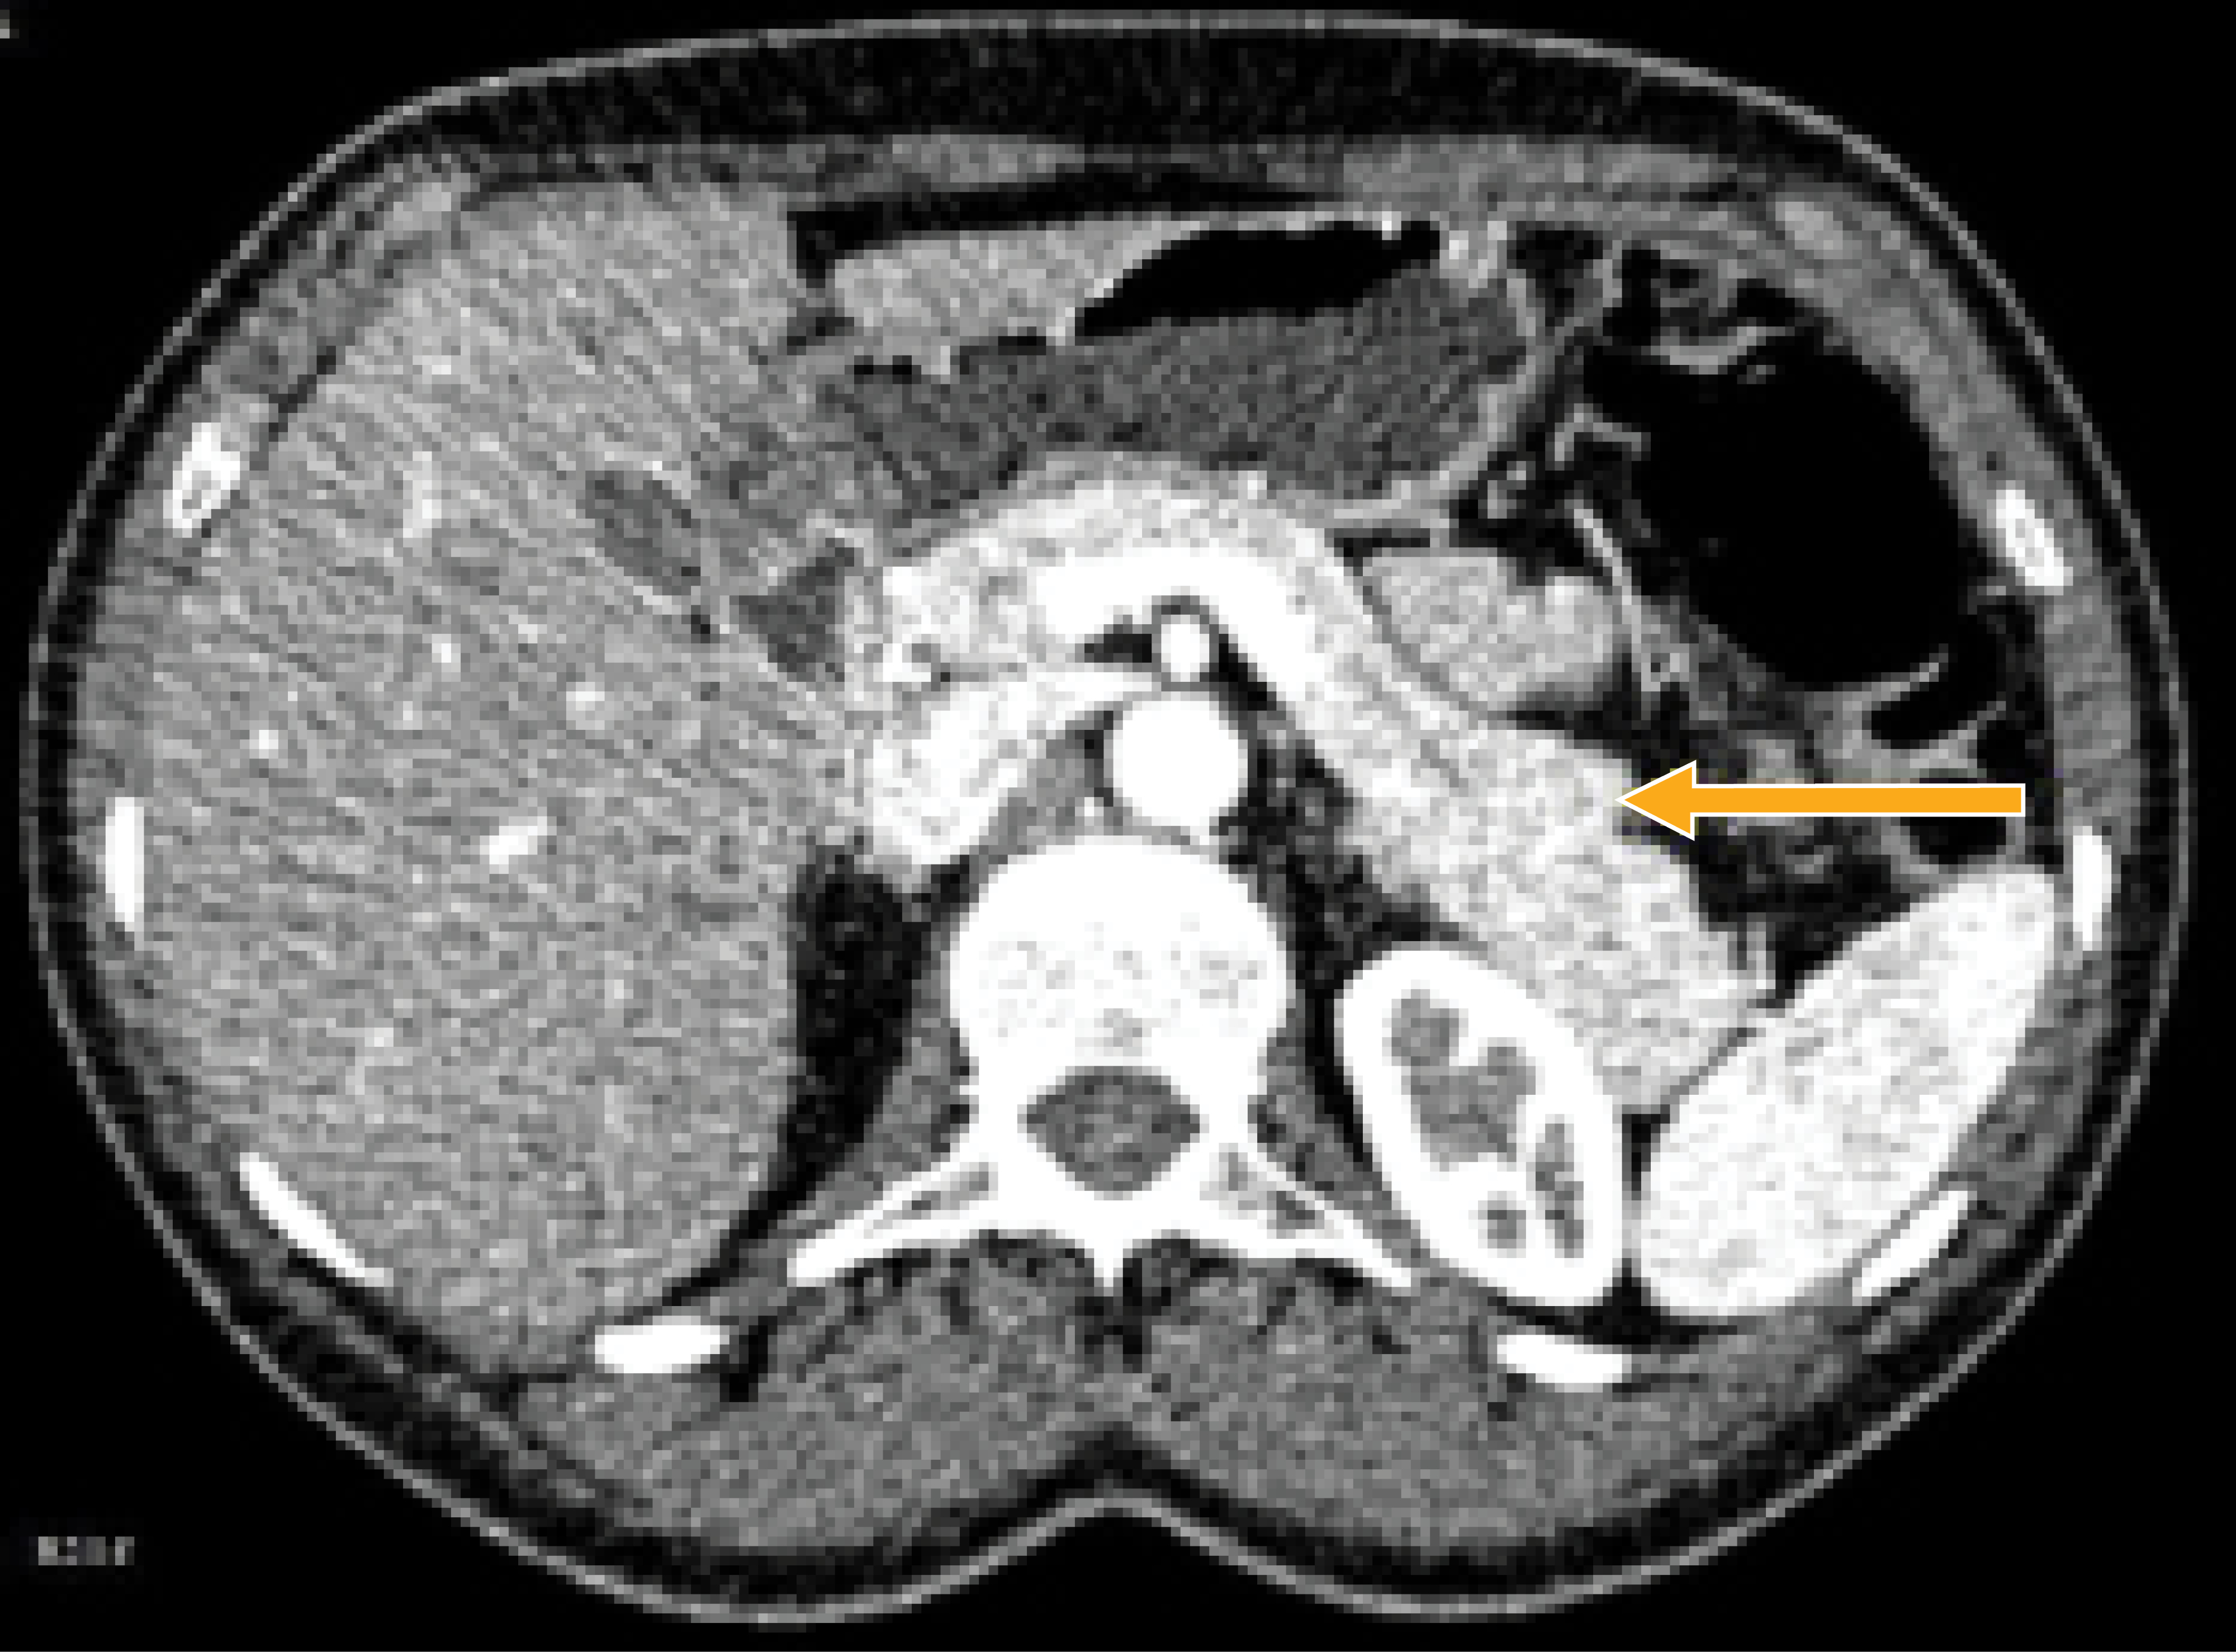

Paciente femenino de 46 años de edad, sin comorbilidades previas y con cesárea a los 23 años de edad como único antecedente quirúrgico. Acude a la consulta externa por cuadro de dolor abdominal crónico y mal localizado, irradiado a fosa renal izquierda, tratado como síndrome de intestino irritable (SII). Dado que no respondió al tratamiento médico estándar para el SII, se realizó tomografía computarizada (TC) simple de abdomen, en donde se observó aumento de tamaño de la cola del páncreas, por lo que se envió al Departamento de Oncología Quirúrgica de nuestro hospital. Para mayor caracterización, se llevaron a cabo varios estudios de sangre e imagen. Los análisis de sangre fueron normales, los niveles de insulina, gastrina y somatostatina también dentro de parámetros normales. Se efectuó tomografía dinámica de páncreas contrastada, donde se observó lesión en la cola del páncreas de 1.9 × 0.9 cm con importante realce del contraste arterial (266 UH) que se mantuvo durante toda la fase venosa (166 UH) y con un lavado tardío como hallazgos (Figura 1). El diagnóstico diferencial fue TNEP-Nf vs bazo accesorio. Dado que la biopsia percutánea no era factible, la endoscópica no estaba disponible y por su tamaño límite, se tomó la decisión de realizar pancreatectomía distal con preservación esplénica laparoscópica asistida por robot.

Figura 1